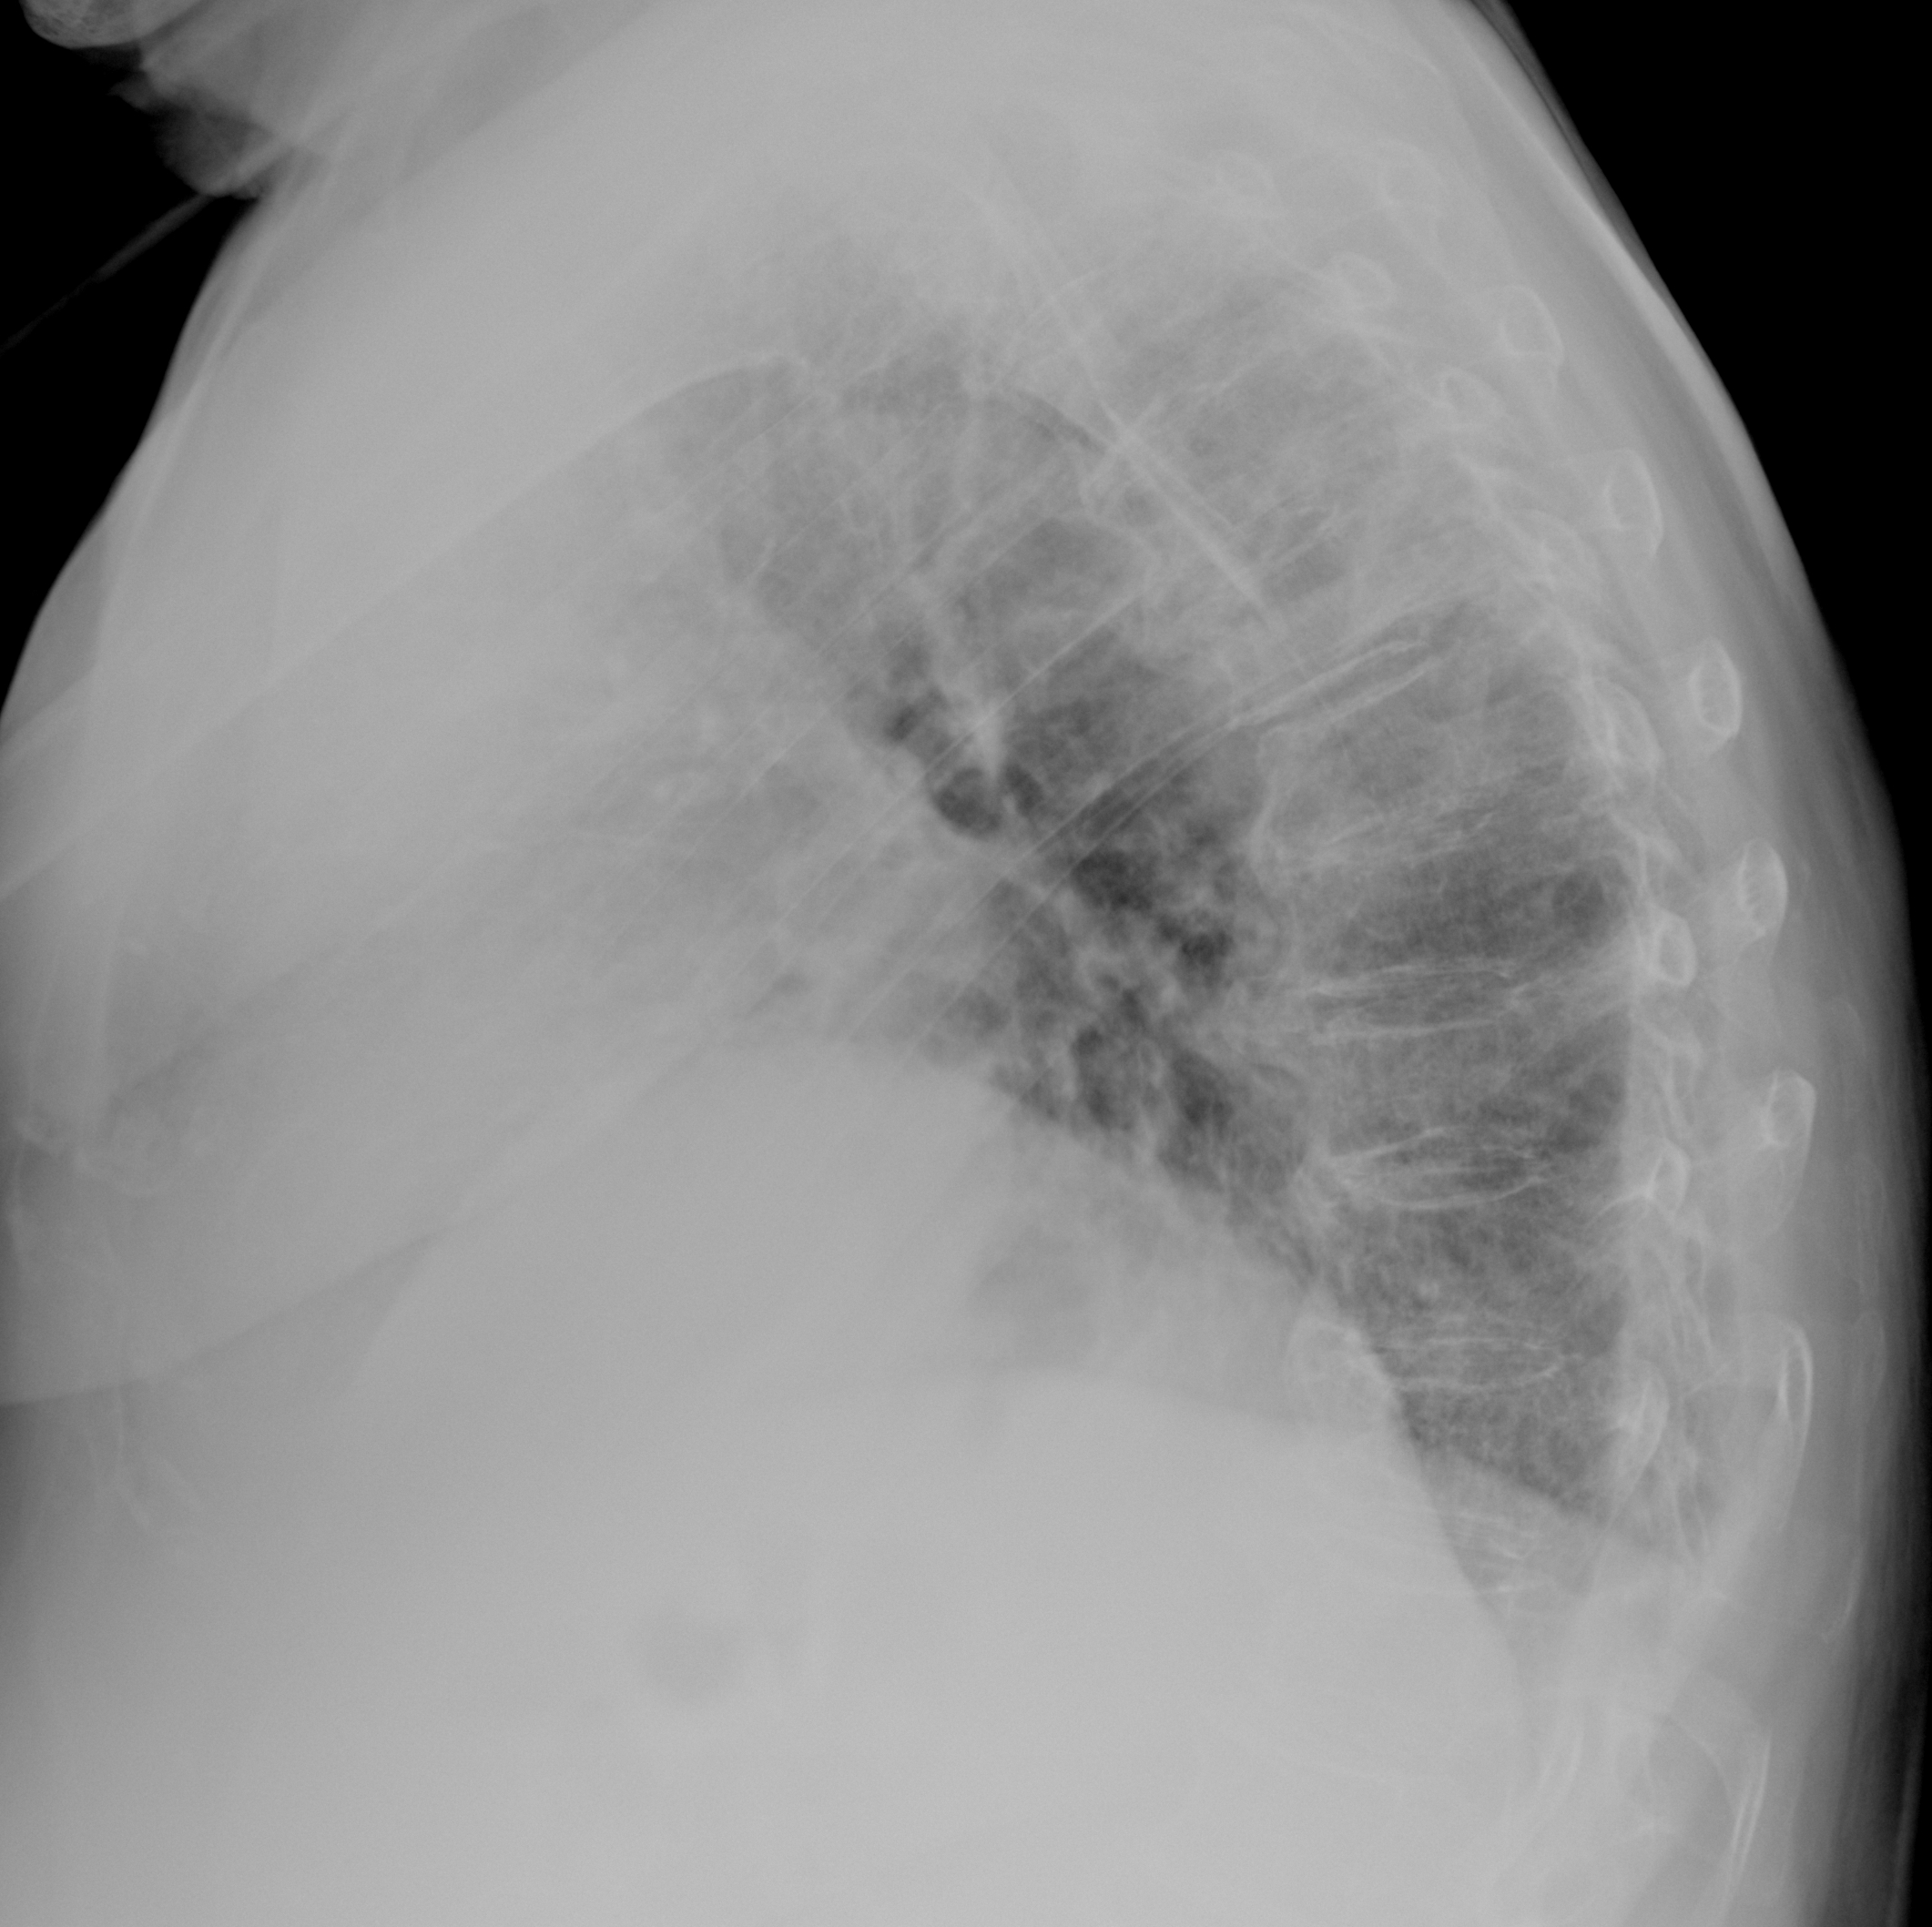

Пневмония

при переломе шейки бедра и пневмонии от компании МосРентген Центр - партнера Института имени Склифосовского